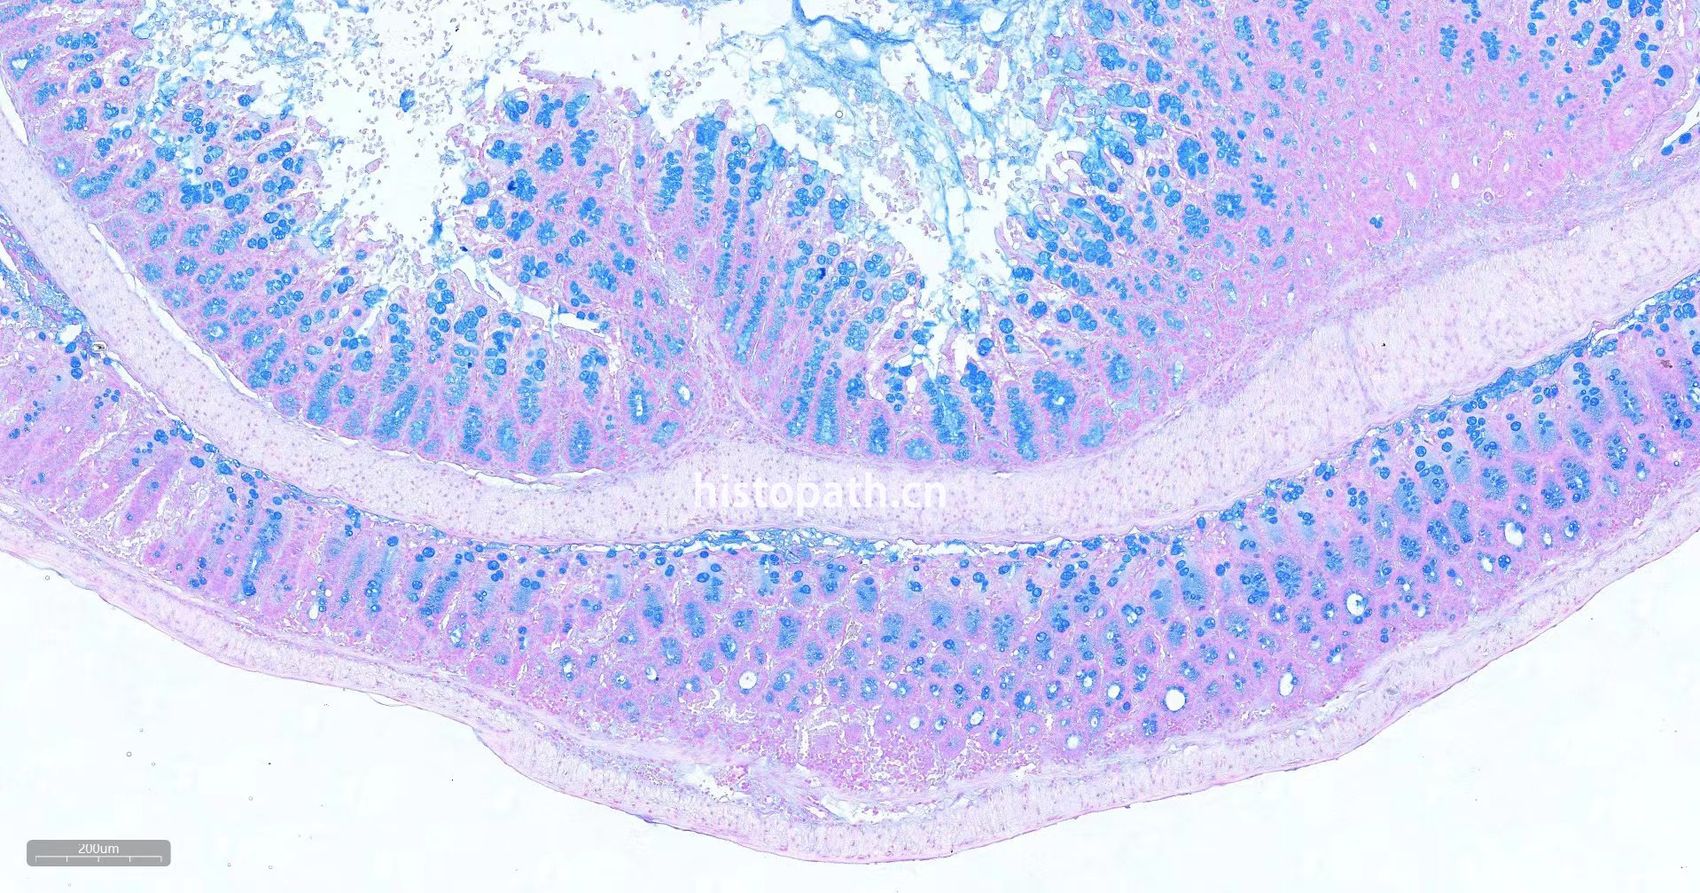

瑞士肠卷详情介绍:取5cm-7cm完整肠道正常固定后用剪刀将肠道剖开PBS涮洗干净肠道内容物后做成瑞士卷肠可观察整个肠道粘膜情况,扩大观察范围,增加切到炎症,溃疡等的几率。

肠卷HE染色

HE-瑞士卷.jpg